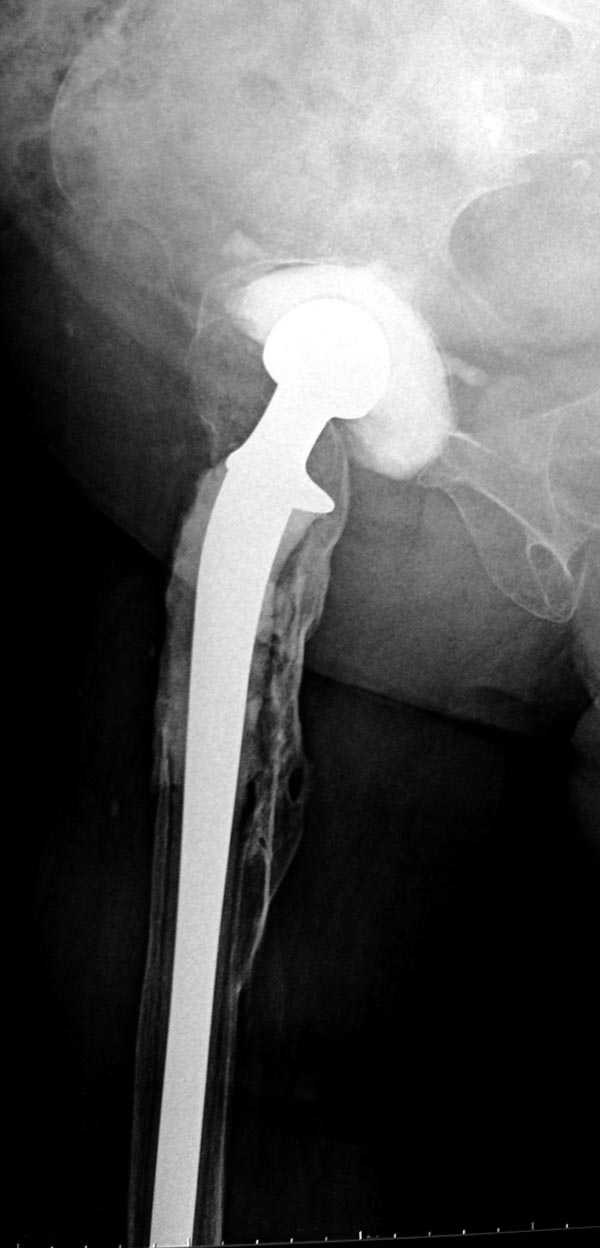

Вот снимки по свежей ситуации, парень 19 лет, длинный оскольчатый перелом бедра от шейки до в-с/3. давно уже ходит на своих ногах.

Dear Евгений.

Представленные Вами рентгенограммы действительно являются примером качественной фиксации спице-стержневым аппаратом. Они, как ни что другое, многое иллюстрируют.

Кроме того, было бы ошибкой ставить знак равенства между нашим и Вашим пациентами. Они не только не похожи, разница между ними просто огромная. Говорю это не для того, чтобы задеть Вас или обидеть. Ни в коем случае. Просто теперь я понимаю, что Ваше мнением строится на простом преломлении Ваших подходов к лечению пациентов со свежими переломами, на ситуацию, абсолютно несопоставимую, подобную нашей.